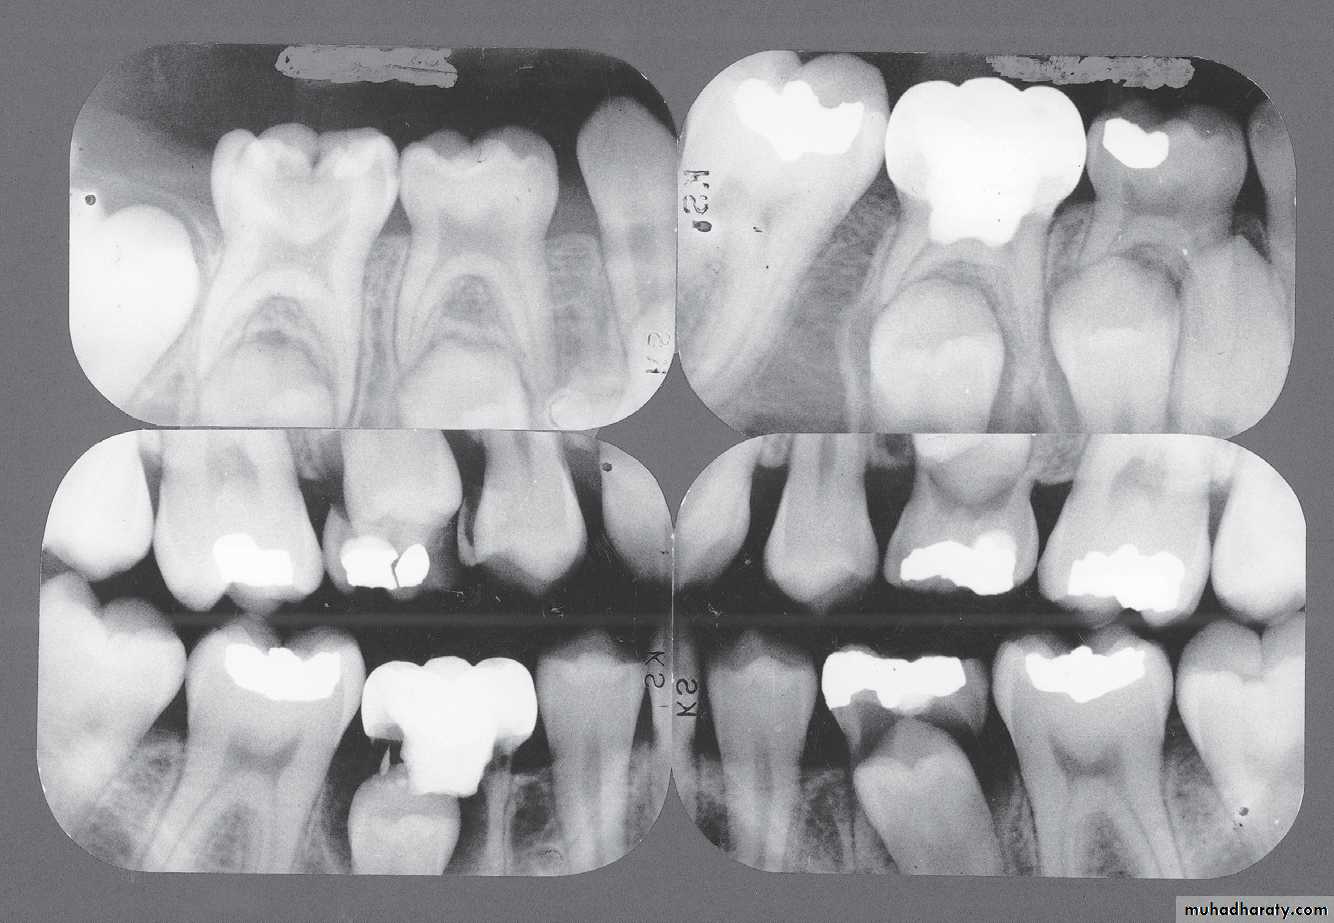

• Bite Wing RadiographsIndications

• Early detection of incipient interproximal caries• To understand the configuration of the pulp chamber

• Record the width of spaces created by premature

loss of deciduous teeth• Determine the presence or absence of premolar teeth

• To determine the relation of a tooth to the occlusal plane for possibility of tooth Ankylosis• Detect levels of periodontal bone at the interdental area

• Detect secondary cariesPosterior bite wing Radiograph

Record the width of spaces created by prematureloss of deciduous teeth

Indications of bite wing radiograph

(A) Interproximal caries detection;

(B) Evaluate the interdental bone